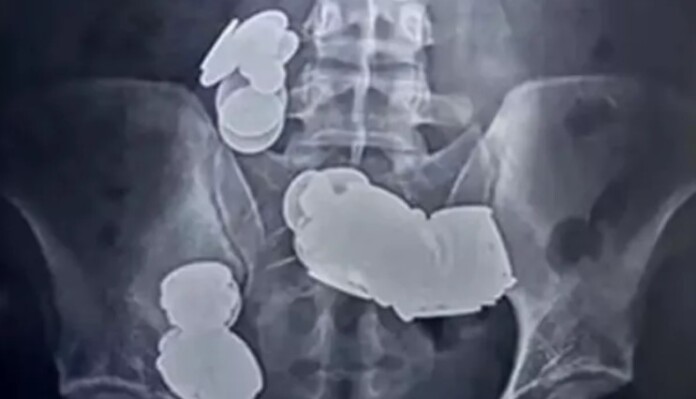

O caso veio à tona quando ele procurou o pronto-socorro devido à falta de alimentação e dores abdominais intensas. No Hospital Sir Ganga Ram, a radiografia abdominal revelou os mais de 70 objetos ingeridos.